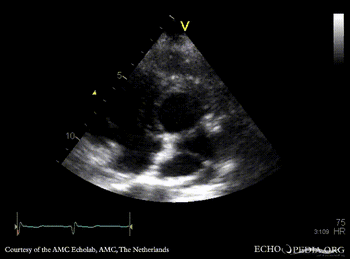

E00578.jpg

Pulsed-wave signal of pulmonary veins flow PSAX: dilated coronary sinus